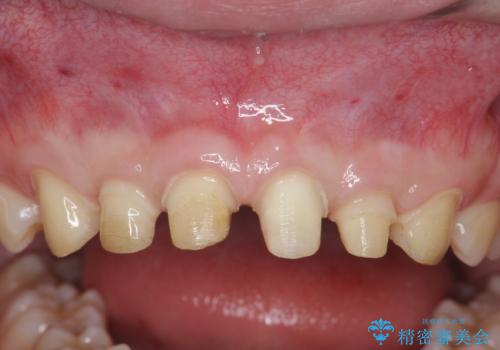

ただ、白いオールセラミッククラウンを製作・装着するのではなく、将来にわたり安定した状況を獲得するため、歯周外科を行い歯ぐきと周囲の歯槽骨の形態を整えていきます。

- 95.7万円(ジルコニアクラウン×6・仮歯×6・歯周外科 )費用は治療当時の料金となります

歯周外科を行ったことで、歯ぐきの形態や腫れが改善され、審美性だけでなく清掃性も大きく改善することができました。